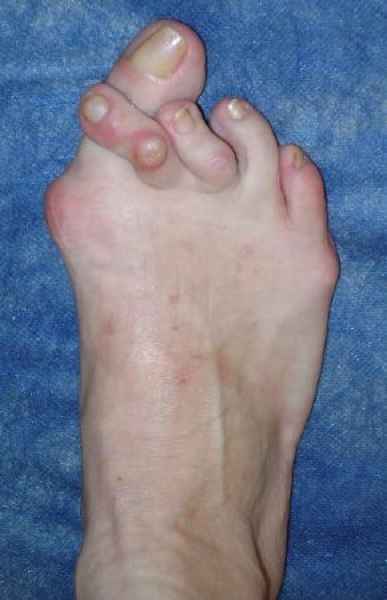

La marcha no solo es característica de la especie humana sino también de cada persona, y más aún varía según el estado de ánimo del momento. Una patología en los pies, se traduce en el rostro, en el ánimo, en el psiquismo. No sólo el dolor produce estos efectos, también un pie deformado o poco estético. En nuestra sociedad, la estética constituye un valor muy apreciado y estas alteraciones causan vergüenza fundamentalmente en las mujeres, que esconden en la playa sus pies en la arena y no pueden usar calzados elegantes.